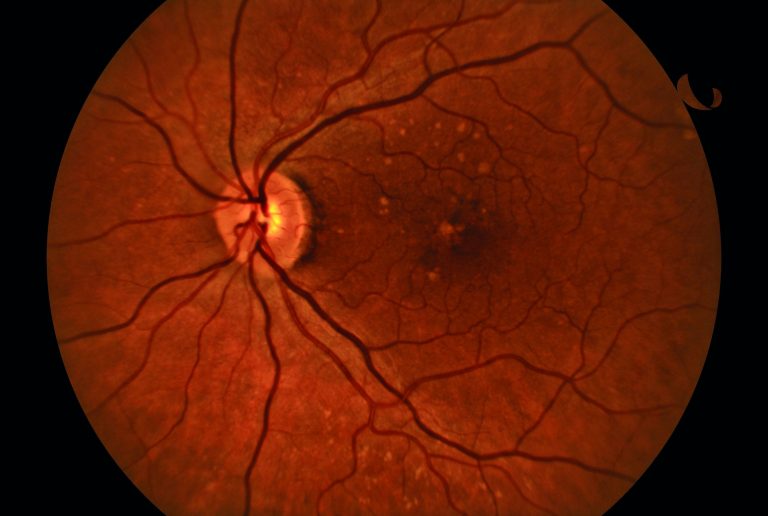

Fond d’œil

Segment postérieur

• Caméra fond de l’oeil non-mydriatique

• Toutes les données pour l’étude, l’évaluation et le suivi des pathologies du segment postérieur

Glaucome

Rétinopathie diabétique

DMLA

Angle du champ de vision

45°

Résolution

6 MP

Résolution optique

> 60 lignes/mm